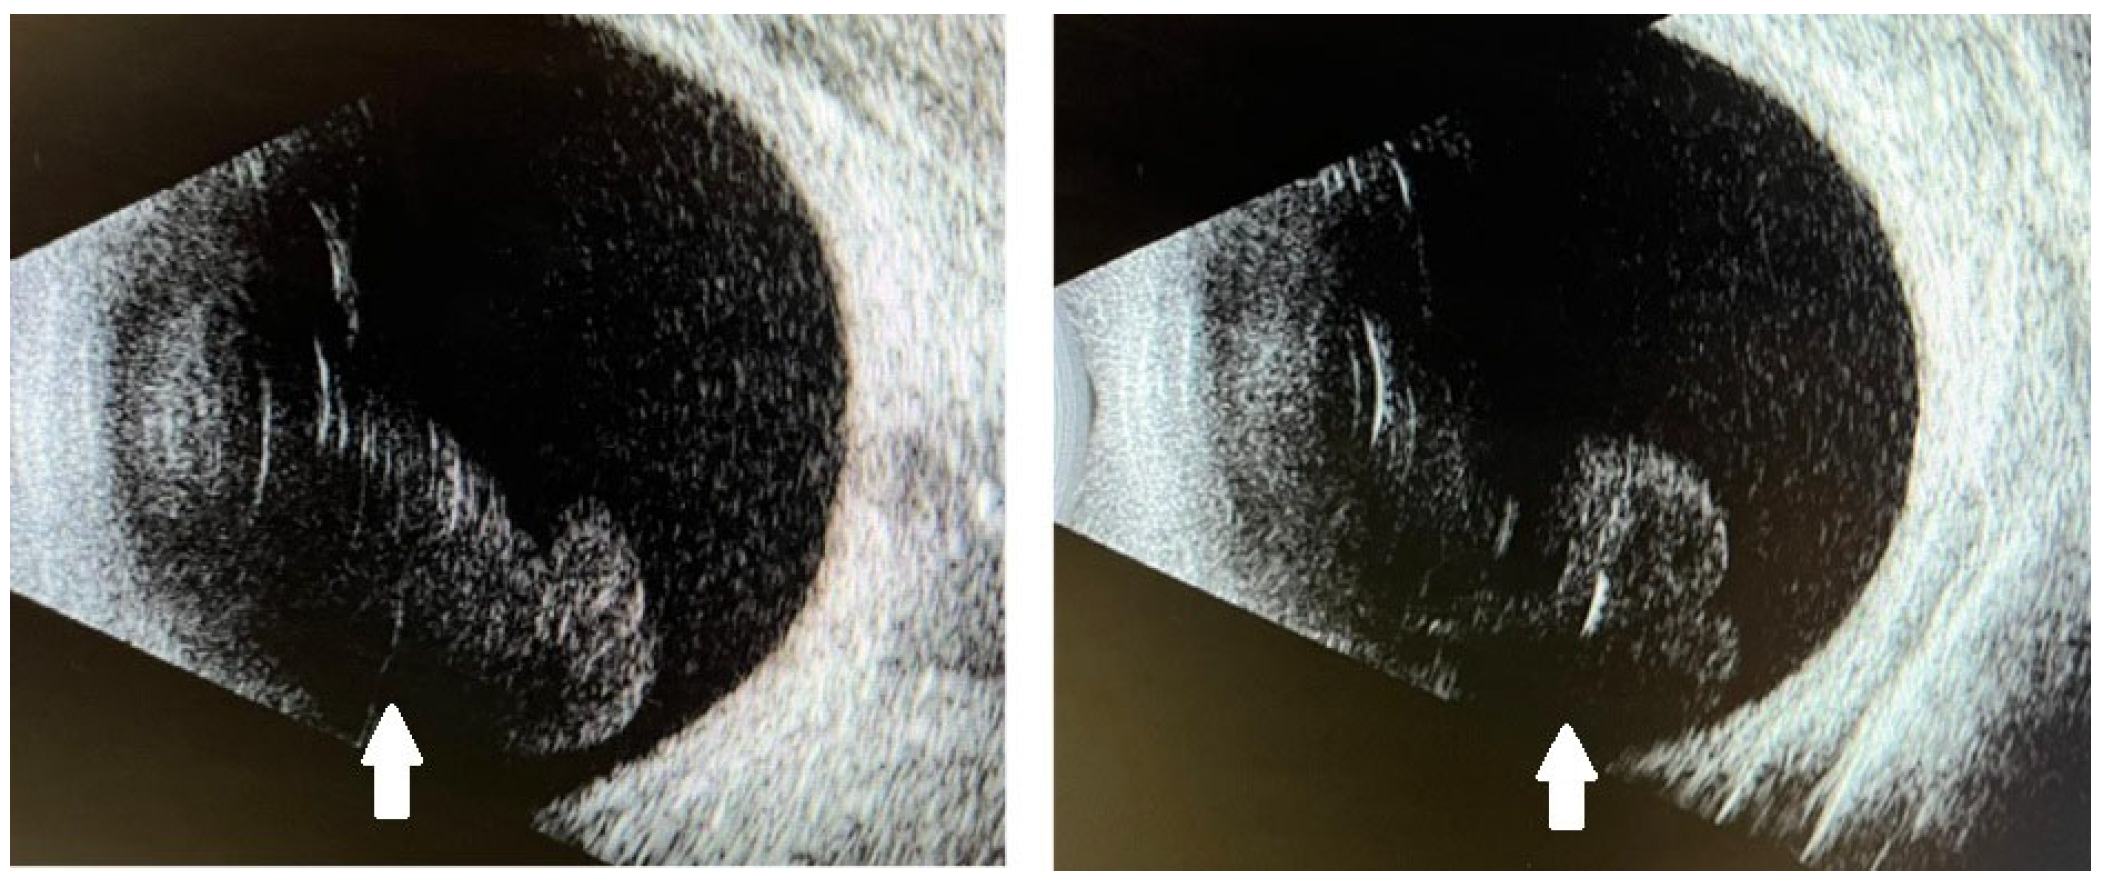

2. Case Report